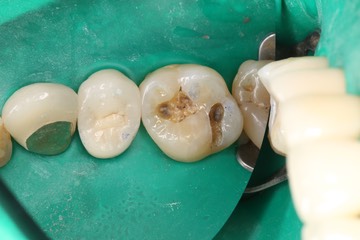

Scott Kanamori #3 caries removal